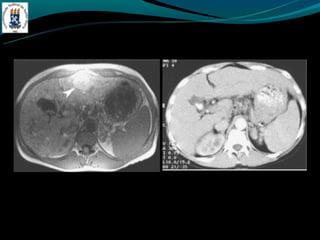

INFARTO HEPÁTICO

-Choque agudo, trauma hipercoagulabilidade

-Elevação da enzimas hepáticas e plaqueta baixa

-Achados: área periférica em forma de cunha, não apresenta

efeito de massa, nem realce pelo contraste.

INFARTO HEPÁTICO -Raro -Choque agudo,trauma hipercoagulabilidade -Elevação da enzimas hepáticas e plaqueta baixa -Achados: área periférica em forma de cunha, não apresenta efeito de massa, nem realce pelo contraste.